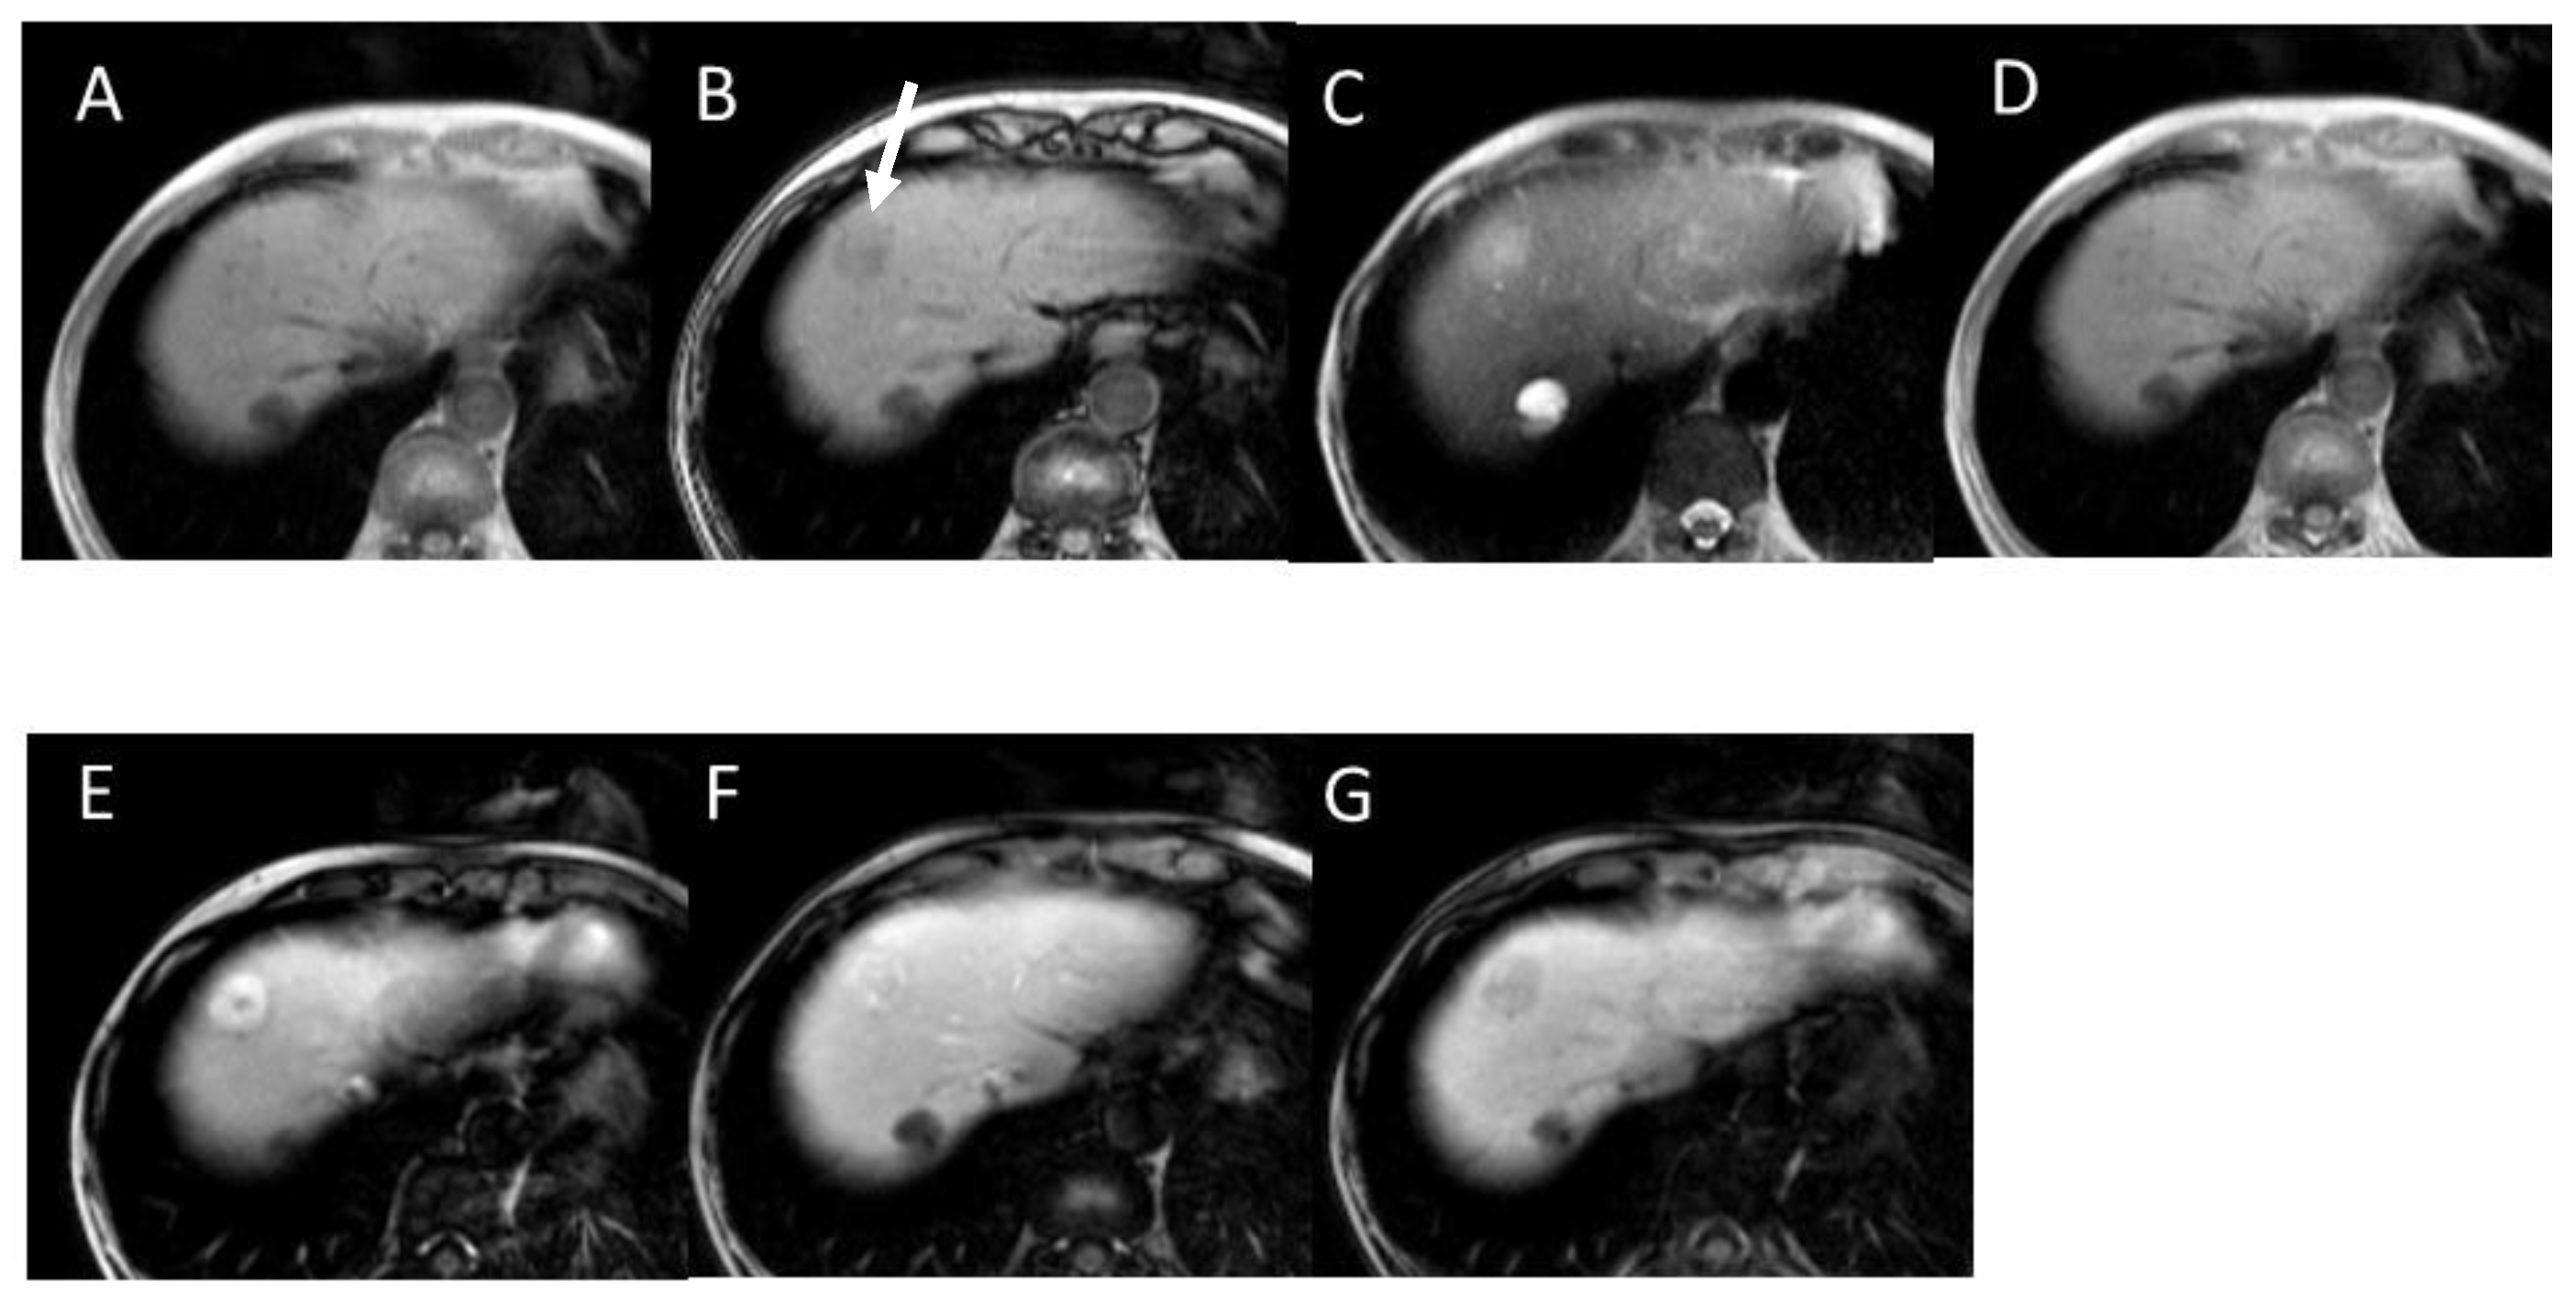

3.6. Gadoxetic Acid Enhanced MRI (EOB-MRI)

4.2. Early Hepatocellular Carcinoma (Early-HCC)

4.3. Well-Differentiated Hepatocellular Carcinoma (Well-HCC)